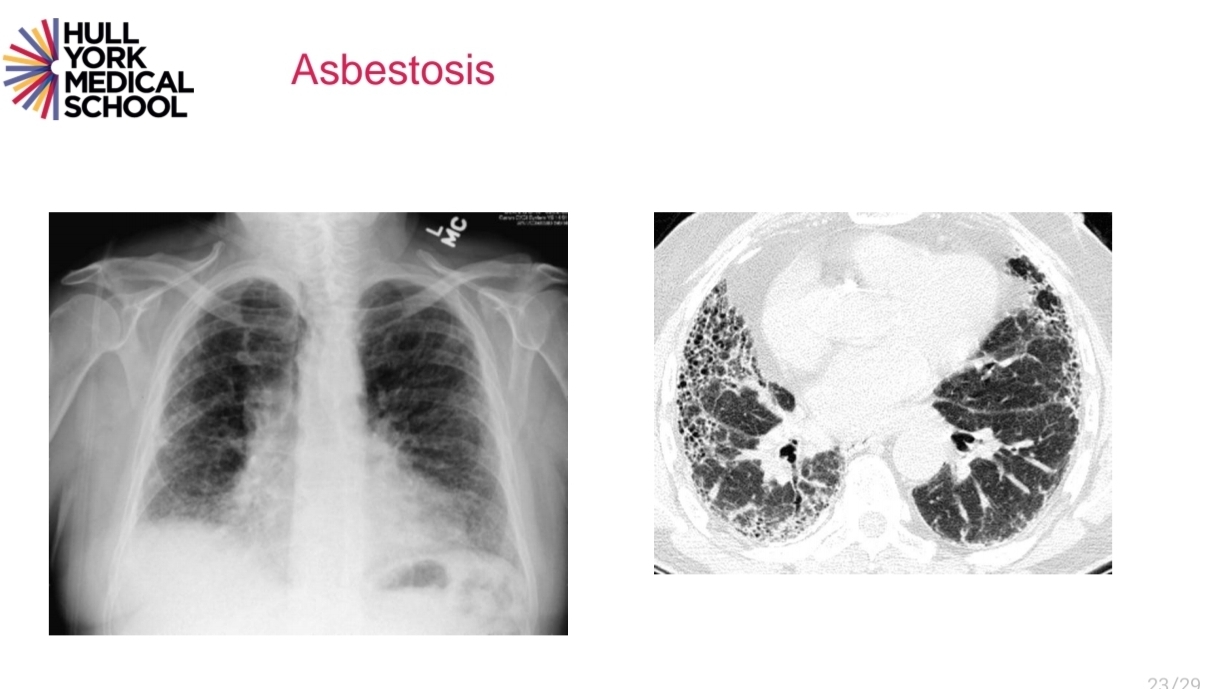

asbestos can cause a range of diseases?

asbtesosis on CXR

A